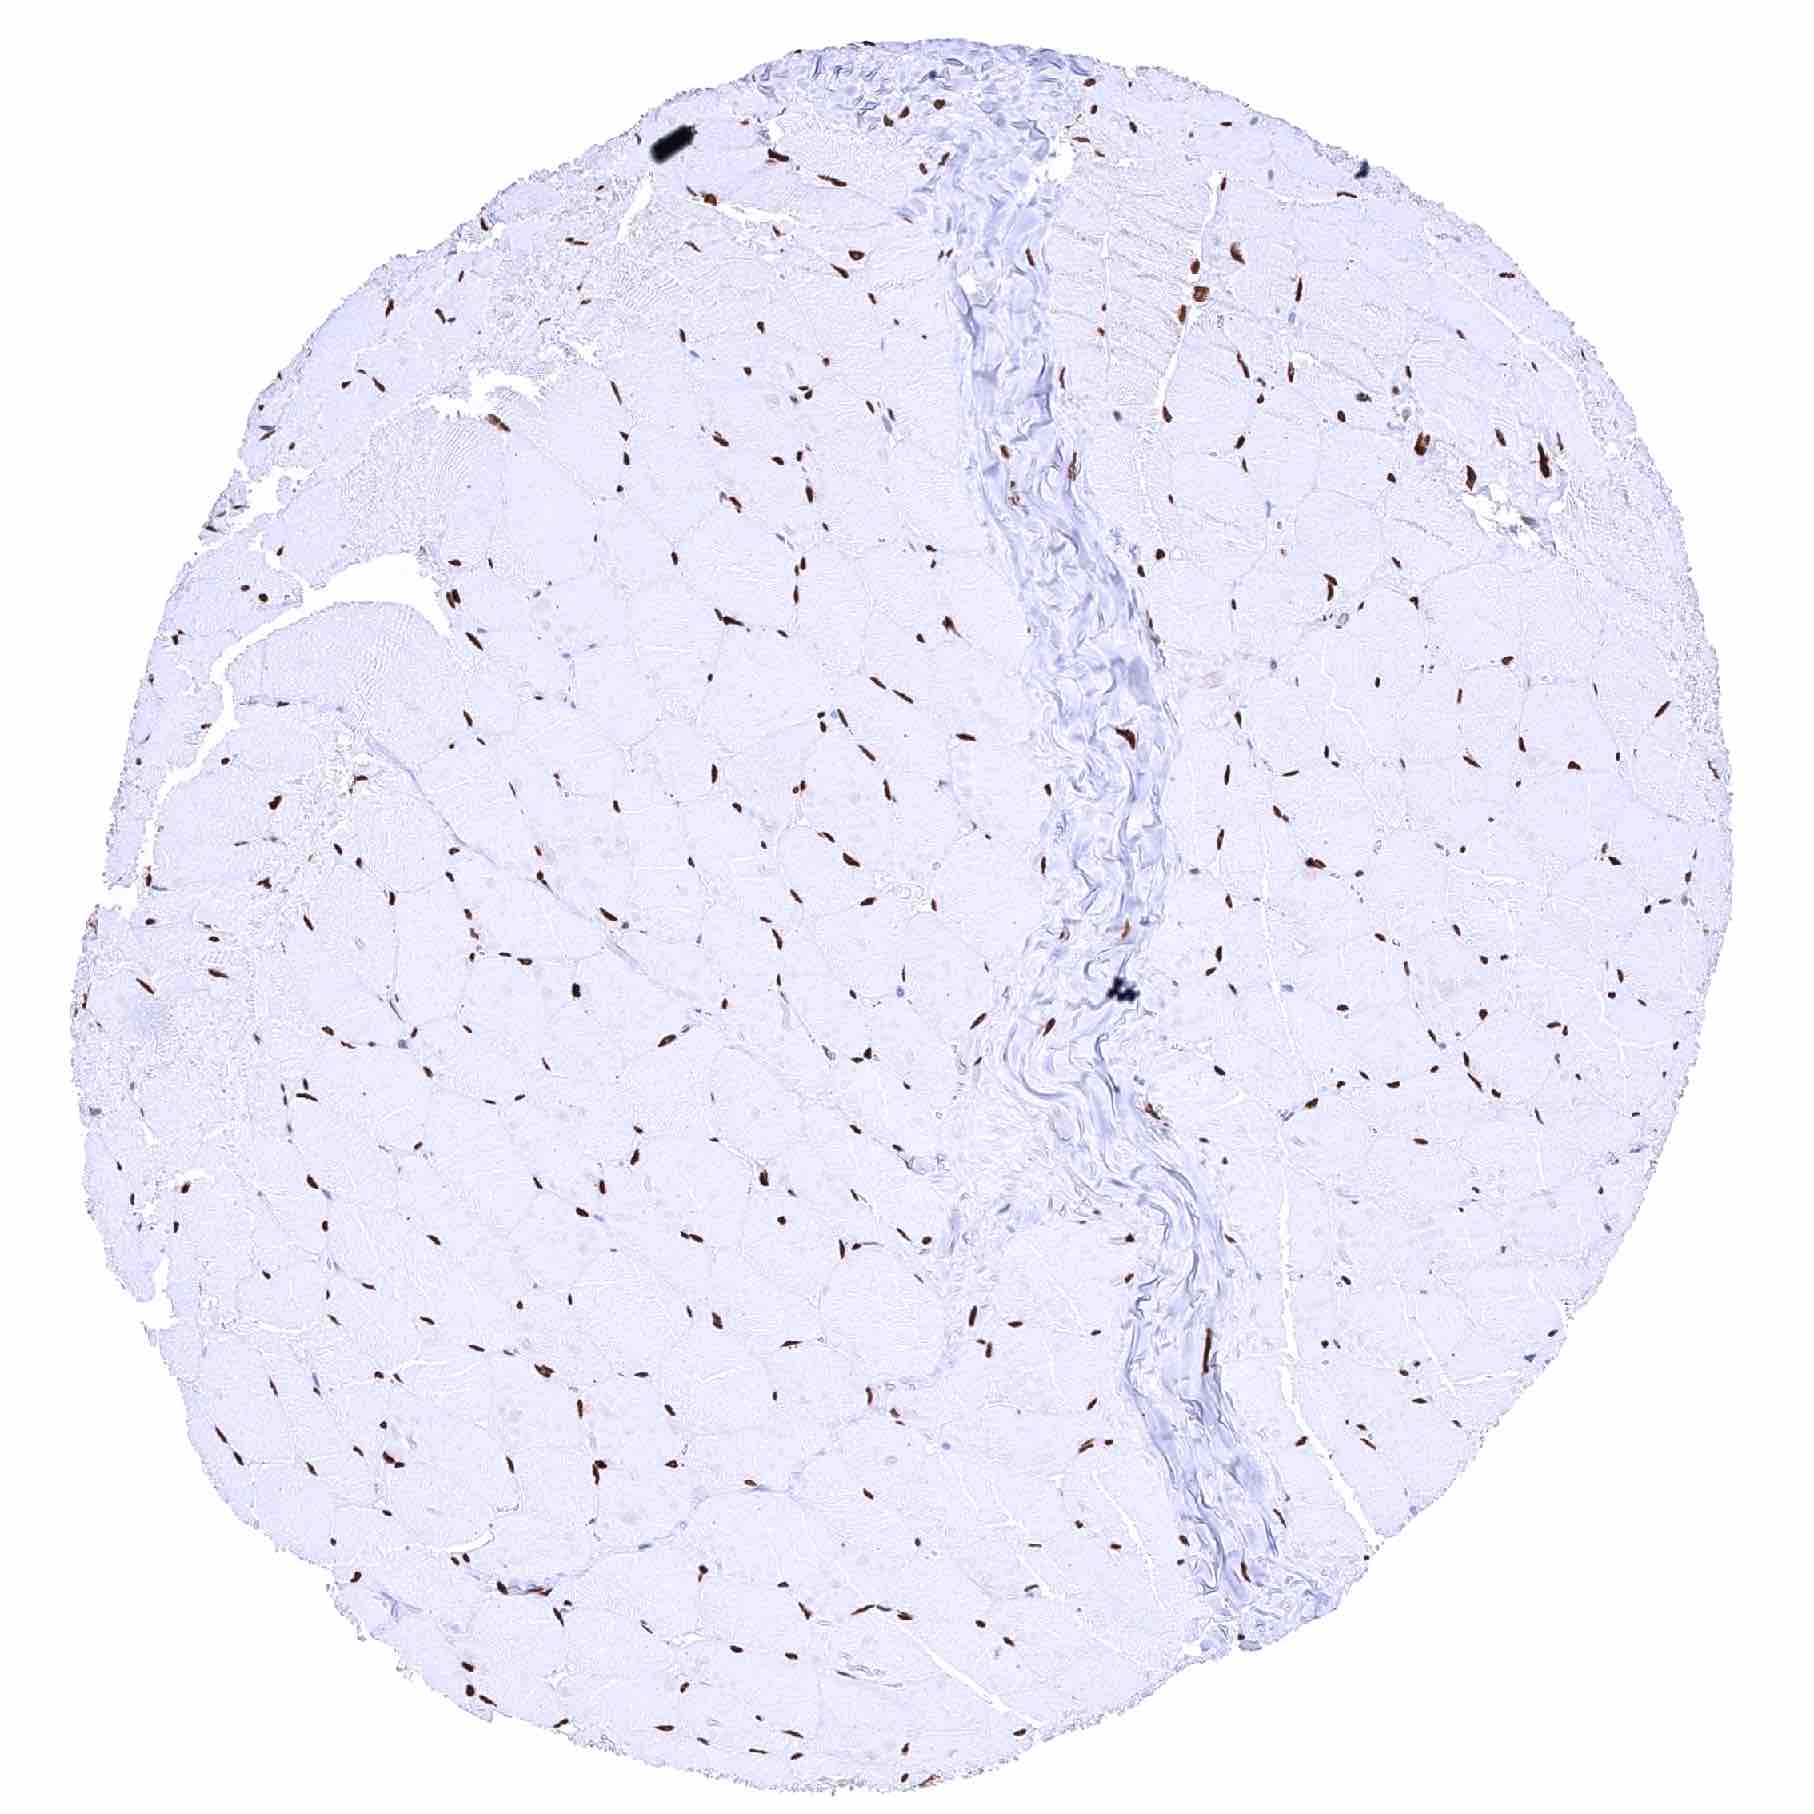

Fat

Skeletal muscle – Distinct nuclear staining of skeletal muscle cells and of other cell types